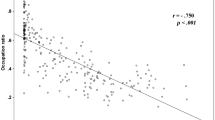

Patient BMI, and related CT image quality, had no impact on the quality of the automatic segmentation. The regression slopes between BMI and Dice coefficient and BMI and Hausdorff distance were both not significantly different from 0 (Fig. 7). In addition, for each of the four RC muscles, Pearson correlation coefficients were very weak for both the Dice coefficient (|r| ≤ 0.15) and Hausdorff distance (|r| ≤ 0.11).